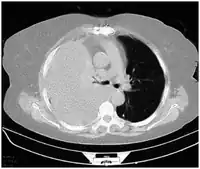

-

Ultrasound scan of the chest showing a left-sided hemothorax -

CT scan of the chest showing a hemothorax caused by warfarin use -

Chest MRI showing a hemothorax in a 16-day-old infant

Computed tomography (CT or CAT) scans may be useful for diagnosing retained hemothorax as this form of imaging can detect much smaller amounts of fluid than a plain chest X-ray. However, CT is less used as a primary means of diagnosis within the trauma setting, as these scans require a critically ill person to be transported to a scanner, are slower, and require the subject to remain supine.[23][26]